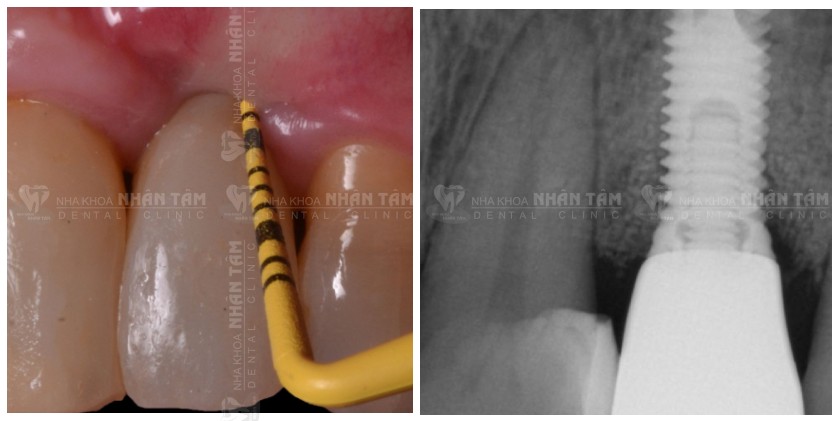

Các bước phẫu thuật:

- Phẫu thuật lật vạt bộc lộ Implant. Bác sĩ sẽ làm sạch mô hạt và vôi bằng dụng cụ chuyên dụng.

- Sử dụng GalvoSurge làm sạch và khử nhiễm bề mặt Implant, giúp Implant và khu vực xung quanh đạt môi trường vô khuẩn.

- Ghép tăng thể thích xương, che phủ với màng tiêu collagen nhằm hạn chế sự xâm lấn của mô mềm sau khi thực hiện ghép xương, đồng thời thúc đẩy quá trình lành thương diễn ra nhanh hơn.

- Sử dụng mảnh ghép mô liên kết để ổn định niêm mạc và hạn chế tụt nướu.

Các bước thực hiện phẫu thuật